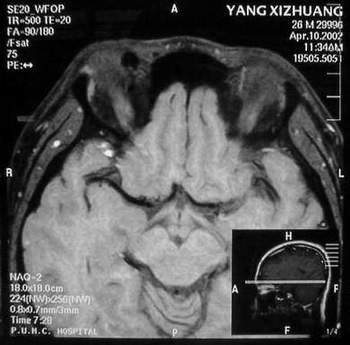

杨某,男,27岁。主因右眼进行性眼球突出一年。我院门诊就诊。发病来,患者无明显视物模糊,无视物成双。自觉无明显眼痛。五年前曾有食物中毒史。当地医院行CT检查,发现右眼眶鼻上方较高密度占位。

门诊检查:视力:双1.5。双眼各方向运动正常。右眼球向正前突出,其中颞侧更明显。右眼穹隆部结膜及近穹隆结膜血管扩张。右鼻上眶缘触及较饱满类结节物,压痛可疑。没有触及博动,听诊未及血管杂音。压迫颈静脉眼球凸度无明显改变。

B 超:球内未见明显异常回声,眶内可见血管暗影回声,视神经上下眶内周围软组织可见各一个血管暗影腔,眶内可见回声不均匀中度密度占位样回声。IMP: 眶内炎性病变?建议MRI除外动静脉瘘,血管性病变。

MRI及增强结果如下:

患者压颈及其它Valsava试验结果阴性。从MRI分析,在T1、T2、T+C检查该支血管均为明显流空现象,说明该血管血流速度很快,而从走行和分布看,眼上静脉可能性很大。也许也不能除外异常的眼动脉或异常血管。眶内主要可能的血管病变包括颈内动脉海绵窦瘘(高流窦)、AVM、眼眶静脉曲张、海绵状血管瘤、静脉性血管瘤、毛细血管瘤和眶内动脉瘤。。